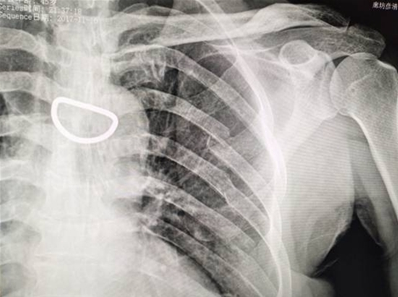

左锁骨外1/3骨折、左肩胛后中线5、6、7肋骨骨折、移位明显。(复位前)